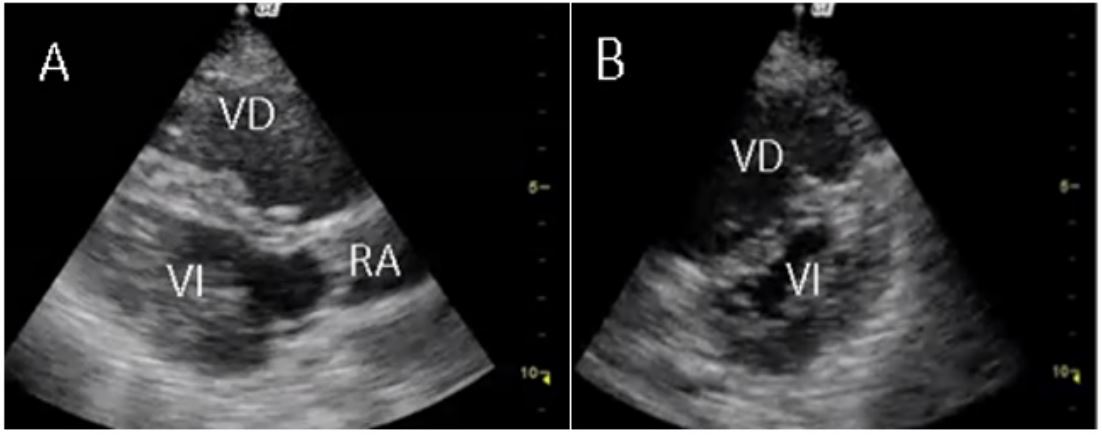

En las salas de reanimación, la paciente tuvo bradicardia extrema súbita y, posterior a ello, paro cardiorrespiratorio, con ritmo de actividad eléctrica sin pulso (AEP); por ello, se le hizo reanimación cardiopulmonar según el protocolo de la Asociación Americana del Corazón y, así, se obtuvo retorno de la circulación espontánea (ROSC). Posterior a ello se indicó el inicio de soporte inotrópico y vasopresor con dobutamina y noradrenalina. Además, con el protocolo CAUSE se trató de enfocar la causa específica del paro cardiorrespiratorio con ritmo no desfibrilable, ya que inicialmente se pensó que su causa era por un posible síndrome coronario agudo, debido a la presencia del bloqueo completo de la rama izquierda. Se encontraron signos indirectos de TEP, en planos paraesternal largo y corto (figura 2a y 2b) y apical de cuatro cámaras (figura 3). Se procedió a la toma de una angiotomografía computarizada de tórax, que confirmó el diagnóstico de TEP agudo con signos de sobrecarga derecha (figura 4); por ello, se procedió a realizar una trombólisis con 50 mg de alteplasa. A pesar de los manejos instaurados, la paciente fallece después de recibir 20 minutos plenos de reanimación cardiopulmonar.

VD: ventrículo derecho; VI: ventrículo izquierdo; RA: raíz aortica.

Para evaluar la presencia de TEP, el examinador debe evaluar los signos de disfunción ventricular derecha, como un VD dilatado y un VI relativamente pequeño (8). El ecocardiograma transtorácico tiene una sensibilidad, especificidad, valor predictivo positivo, valor predictivo negativo y precisión para el diagnóstico de TEP del 75 %, del 89 %, del 92 %, del 67 % y del 80 %, respectivamente (9).

La utilidad del uso del ultrasonido radica en la identificación de datos indirectos de TEP y no del émbolo propiamente dicho (raramente visualizable) (12). Los datos que sugieren sobrecarga del VD son el diámetro ventricular >40 milímetros (mm), disfunción sistólica de moderada a severa y gradiente sistólico tricúspideo mayor a 50 mm de mercurio. Los signos más importantes para el diagnóstico diferencial, aun en presencia de enfermedad cardiorrespiratoria previa y como pronóstico, son el signo de McConell y el signo de 60/60. El signo de McConnell, descrito en 1996, consiste en una marcada alteración regional de la motilidad parietal del VD observada en vista apical cuatro cámaras con acinesia/hipocinesia de los segmentos medios y basales de la pared libre y relativa preservación de la región apical (13). El signo 60/60 es un tiempo de aceleración de la válvula tricúspide menor a 60 milisegundos en presencia de un gradiente sistólico tricúspideo mayor a 30 pero menor a 60 mm de mercurio (14). La coexistencia de un VD hipocinético agrandado con el signo de McConnell, junto con el signo 60/60, parece ser el criterio ecocardiográfico más útil para la disfunción del VD (13).